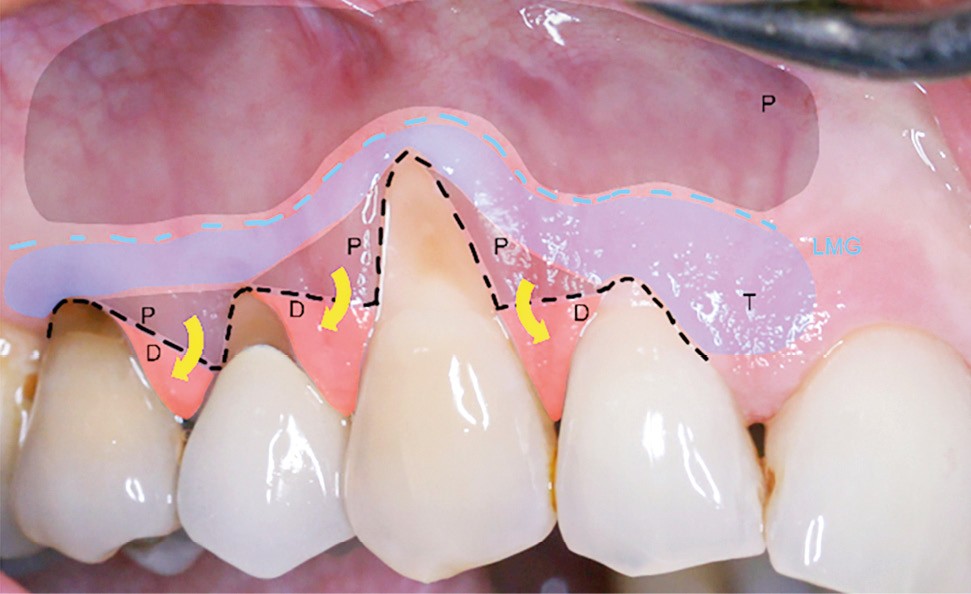

De nombreuses techniques de lambeaux déplacés latéralement, lambeaux déplacés coronairement (fig. 4), enveloppes ou tunnels (fig. 5) ont fait l’objet de publications et présentent des résultats quasi identiques en termes de recouvrement. Leurs points communs sont un recouvrement complet du greffon, une dissection en épaisseur partielle suffisante pour assurer un positionnement du lambeau sans tension et l’absence (quand cela est possible) d’incision de décharge. Le choix d’une ou l’autre technique dépend surtout de l’expérience du praticien et de la quantité de tissu disponible apicalement ou latéralement.